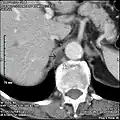

Scanner lombaire: Citerne du chyle (flèche pleine) à proximité de la veine azygos (flèche vide).